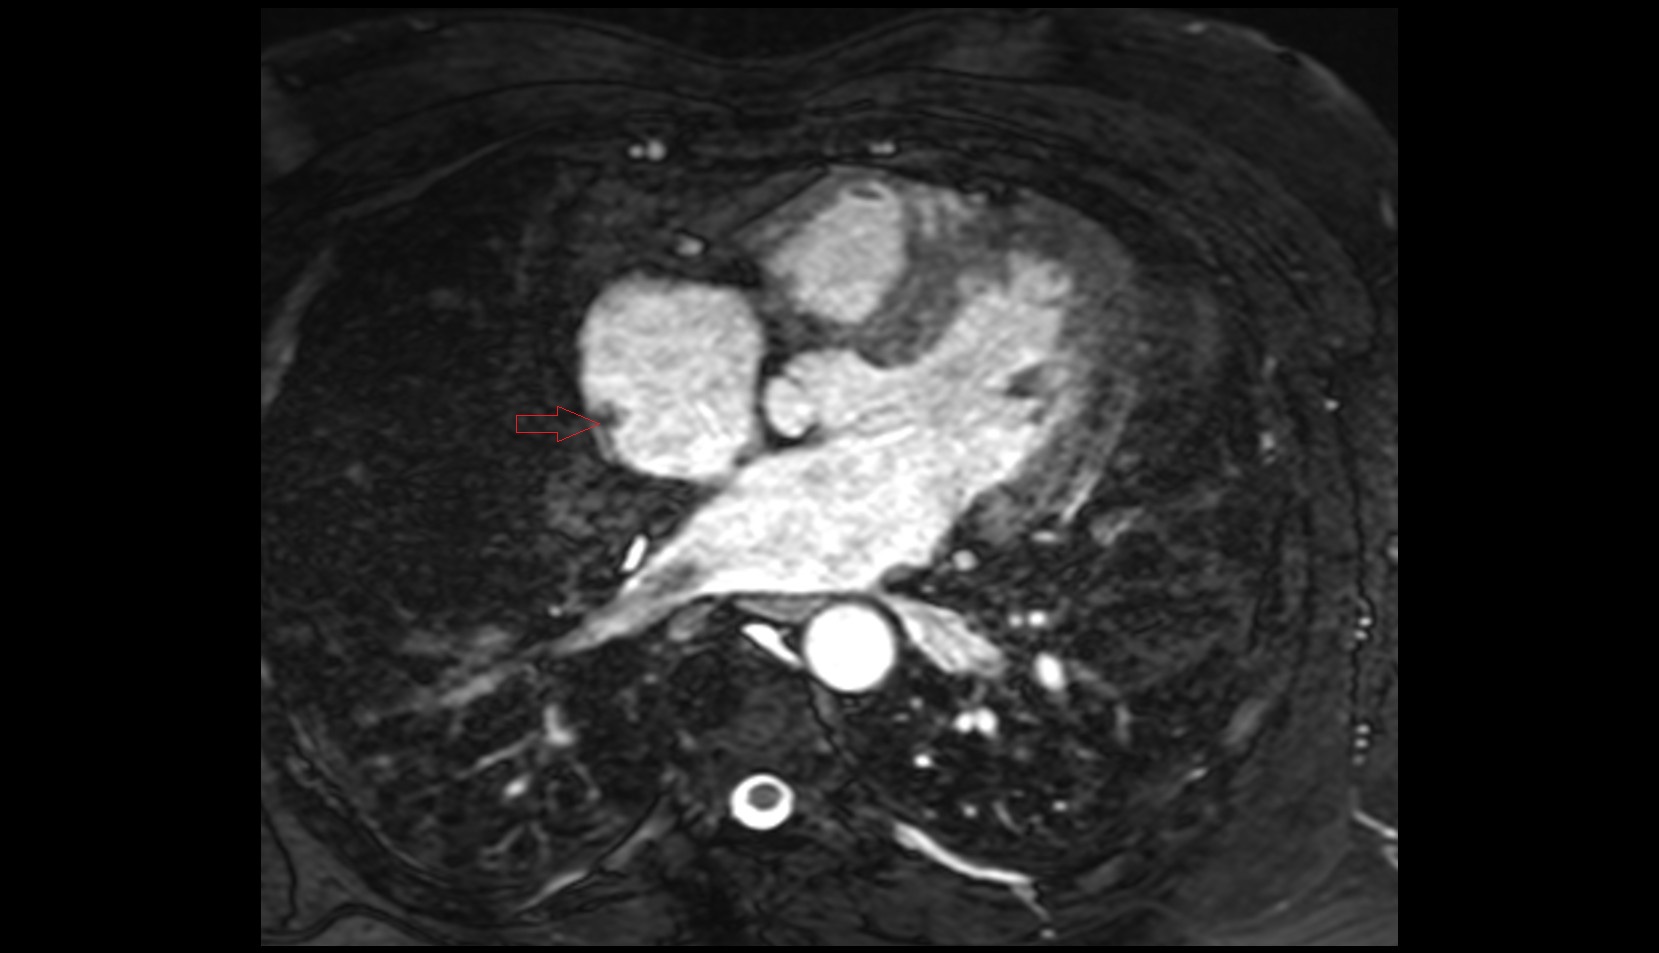

- Heart

- Left ventricle

- Right atrium

- Left atrium

- Right ventricle

- Interventricular Septum

- Left atrioventricular valve (mitral or bicuspid valve)

- Right atrioventricular valve (tricuspid valve)